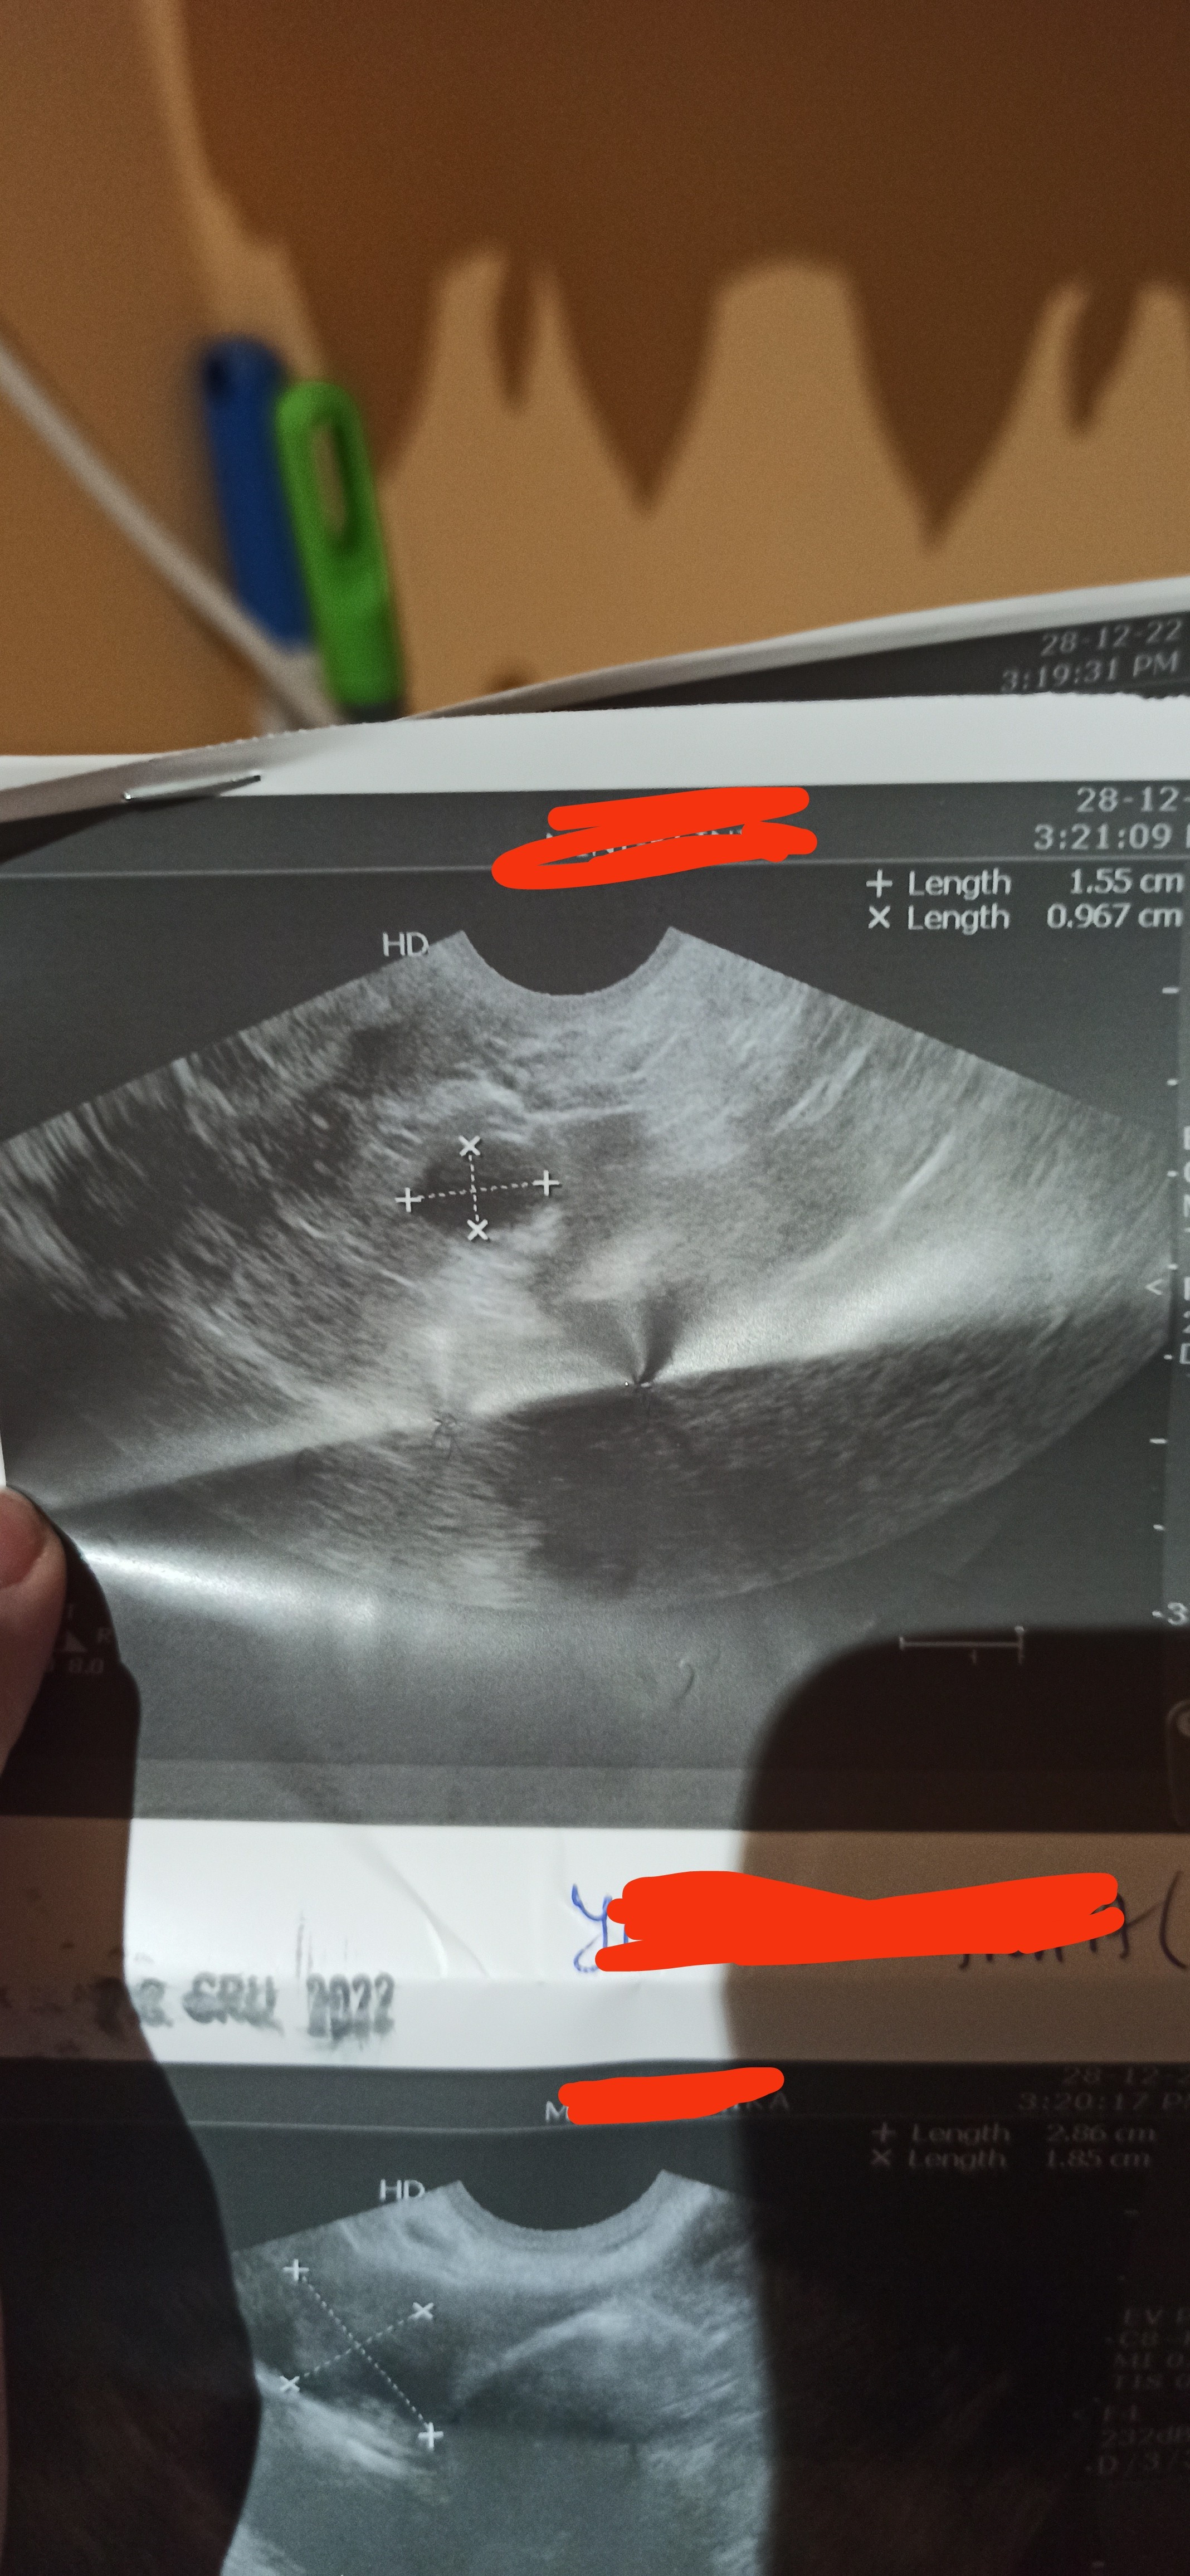

Zdjęcie usg torbiel? Ciemny punkt

mial ktoś coś podobnego? Mi to wygląda bardziej na jakiś pęcherzyk

Lekarz że torbiel w jajniku ale może któraś miała podobnie. pierwszy raz na USG u siebie widzę takie coś.. Nw co myśleć. Niby sam zniknie ale jednak kontrolować i przyjść więc ta gadka to takie masło maślane nie jestem w stu procentach pewna tej diagnozy.